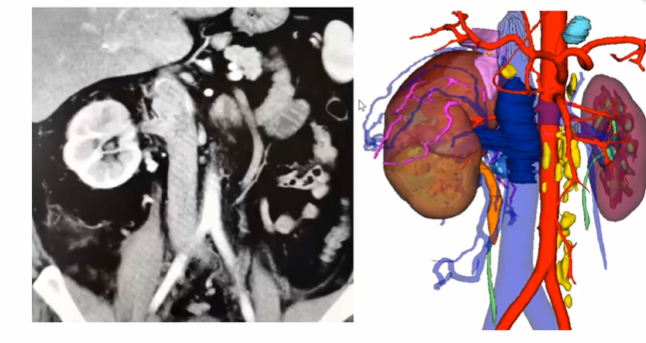

从先处理肾动脉到先离断IVC+切开取栓

既往手术切除肾脏我们通常都会先处理肾动脉,但事实上有相当一部分患者可以先切断下腔静脉,再处理肾动脉,这样的病例在临床中也比较常见。如下图所示,当患者瘤栓充满血栓后,没有很好的空间去寻找肾动脉,此时我们可以先离断下腔静脉,这样就有足够的空间,再去取瘤栓和切断肾动脉就会变得简单便捷。当前这种模式本科室也已成为一种常规的术式,通过这种方式可以简化手术步骤,同时也可以很好地处理掉肾动脉。